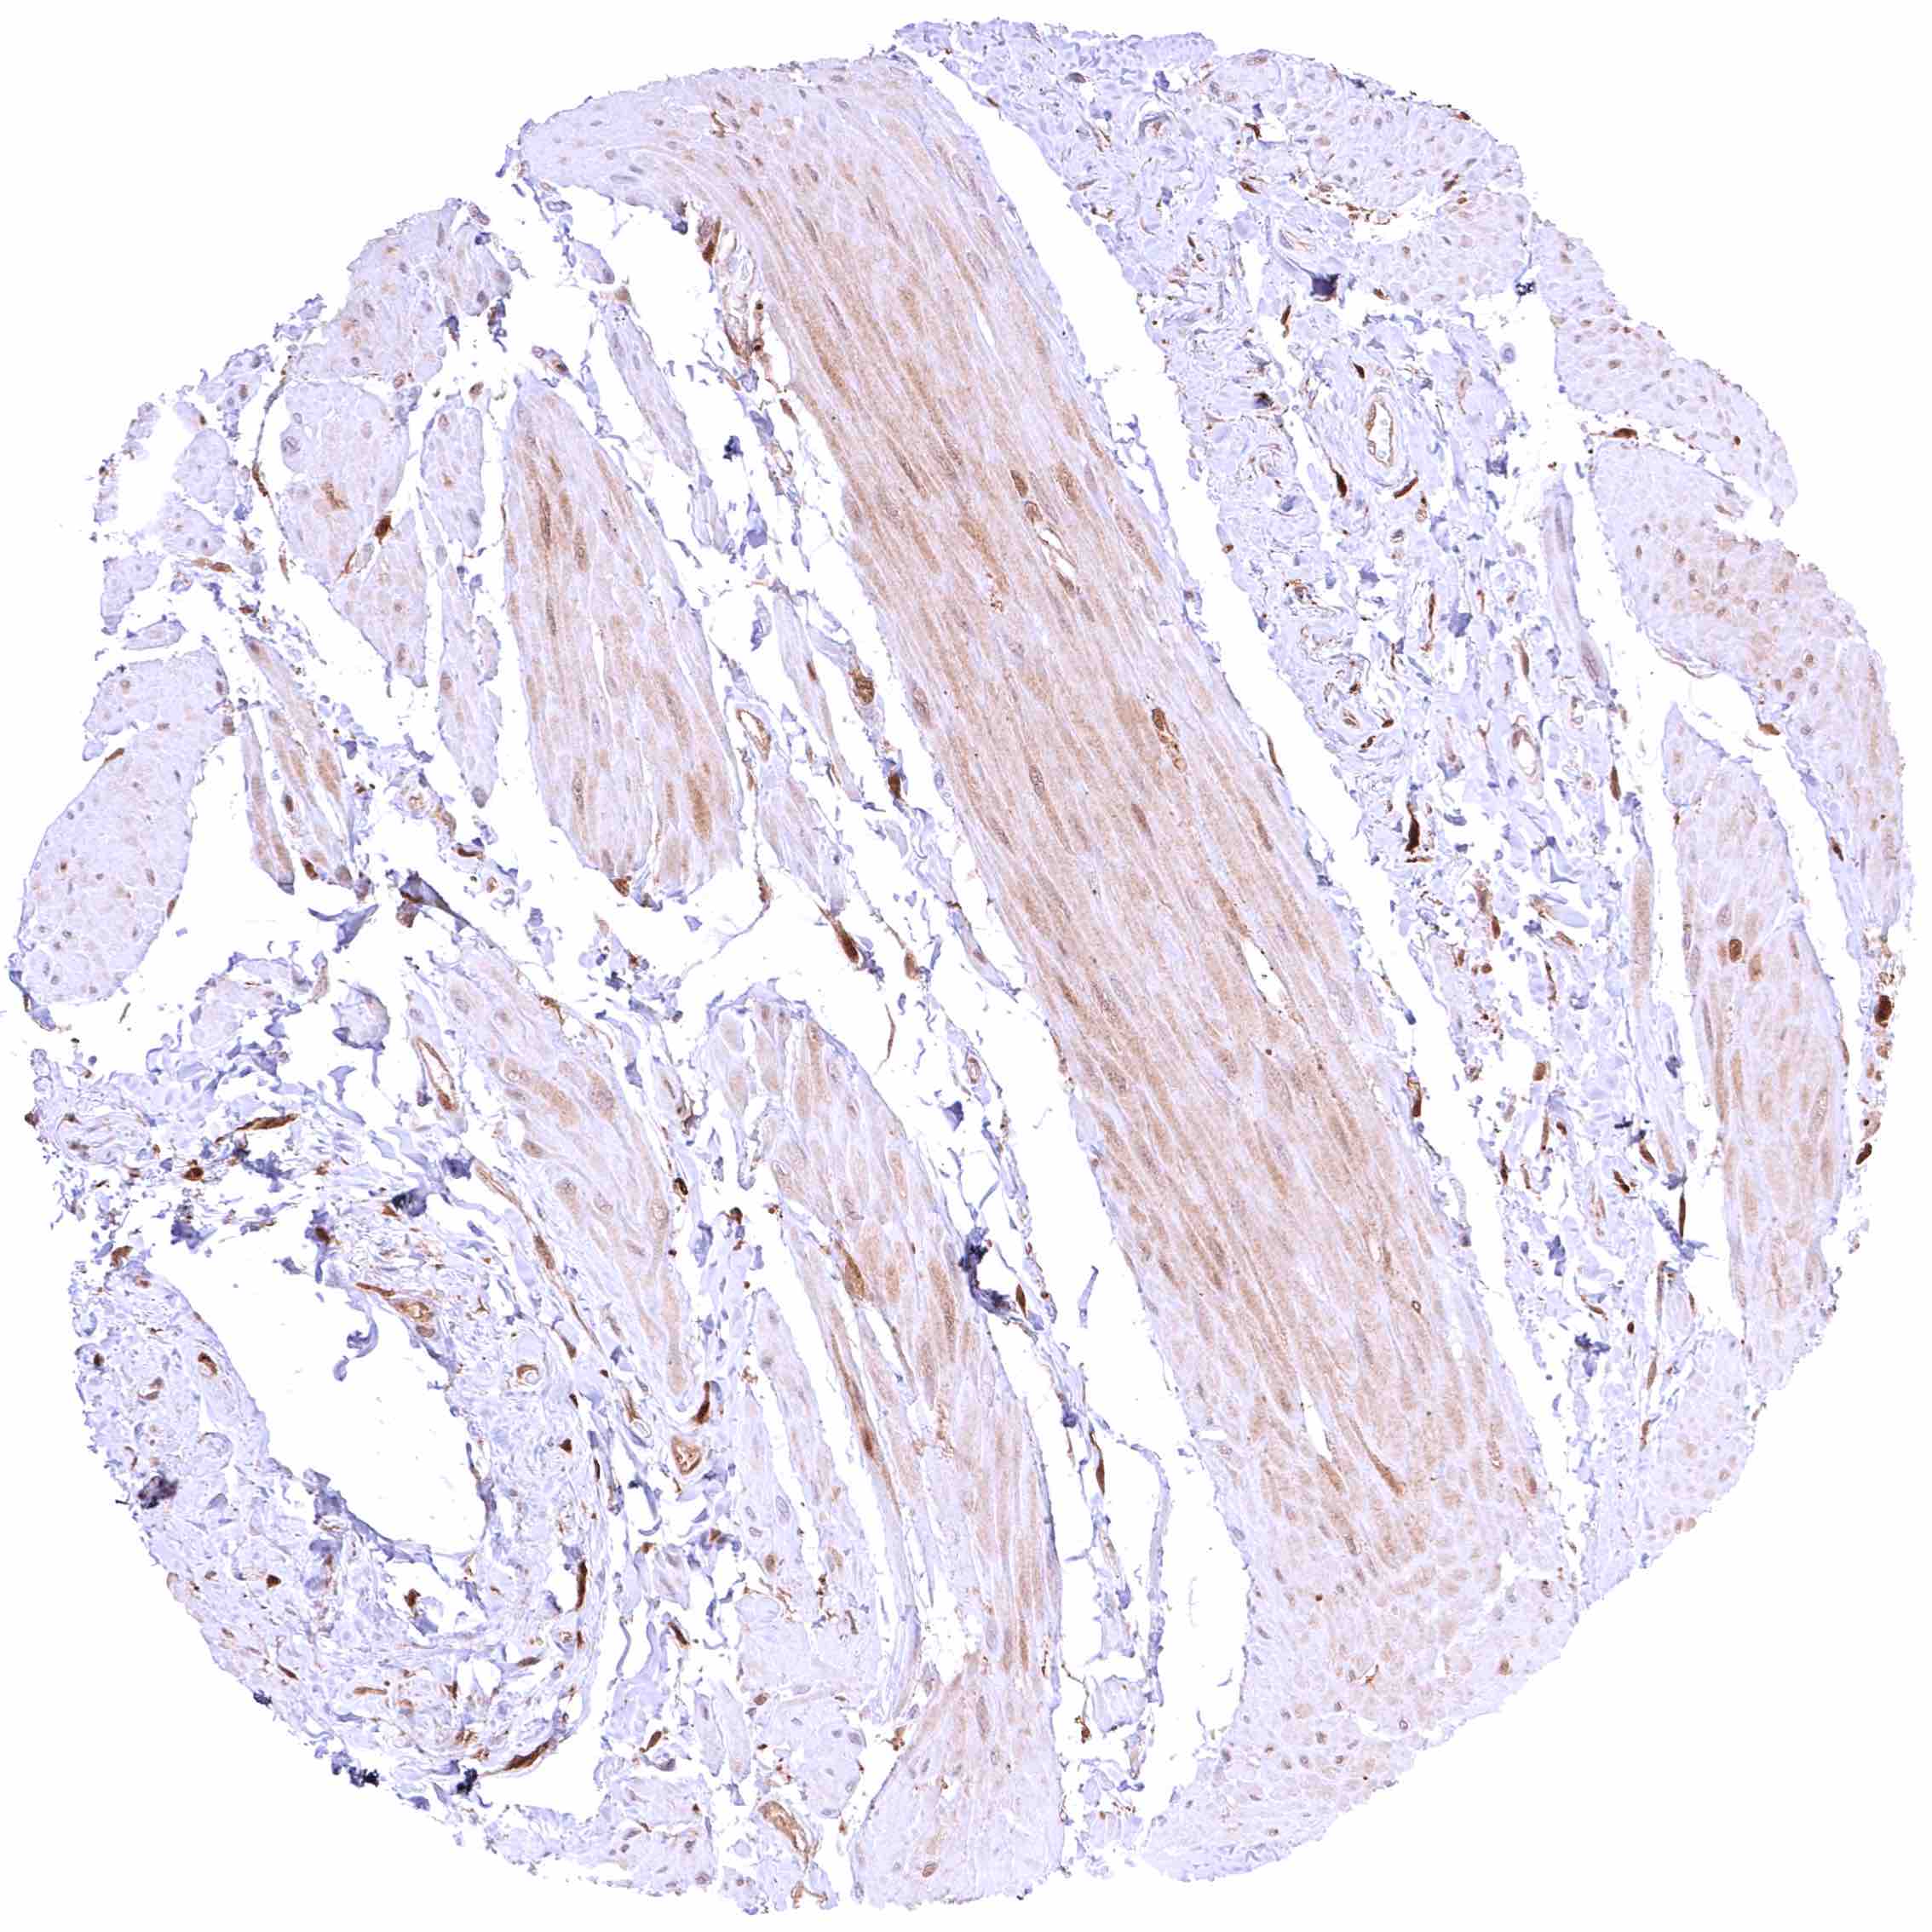

Skeletal muscle – Most GSTP1 staining occurs around small capillaries while the muscle cells are GSTP1 negative.